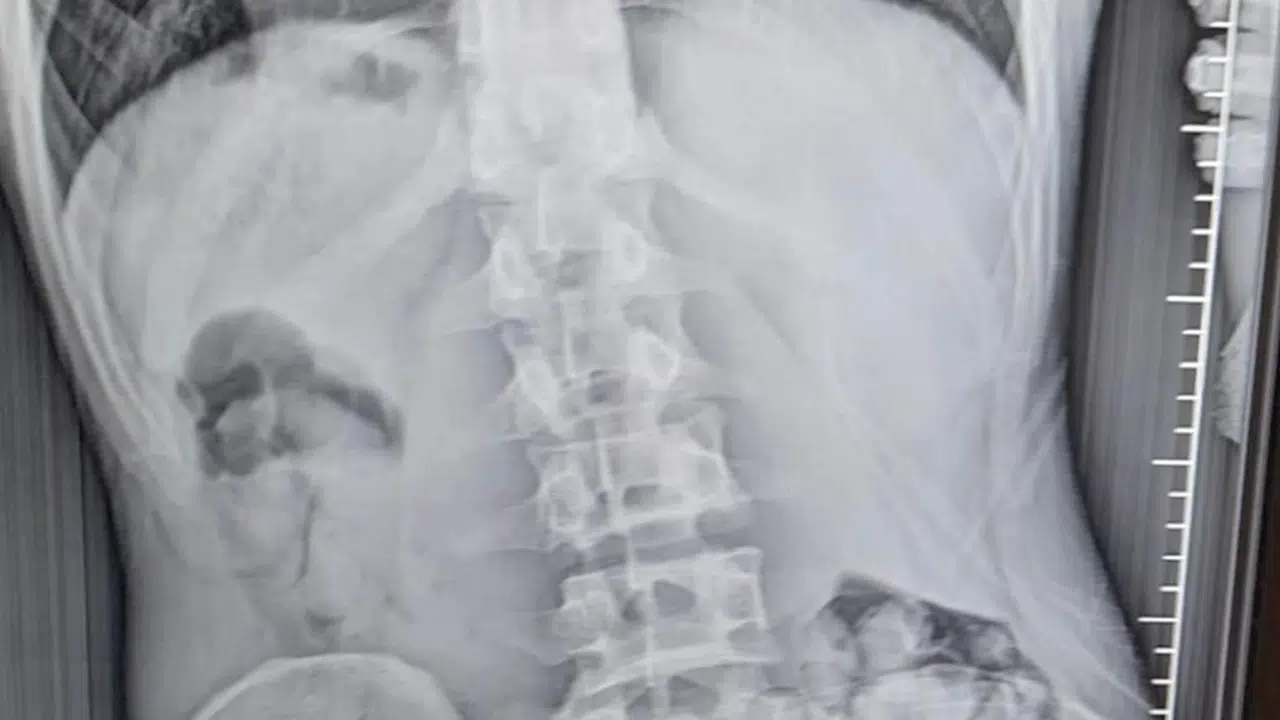

Emre ÖNCEL/SAMSUN, (DHA)- SAMSUN’un Çarşamba ilçesinde midesinde 51 kapsül halinde 309 gram uyuşturucu olduğu tespit edilen R.B. (21), gözaltına alındı.

İl Emniyet Müdürlüğü Narkotik Suçlarla Mücadele Şube Müdürlüğü ekipleri, R.B.’nin, Van’dan Samsun’a yolcu otobüsüyle uyuşturucu getireceği bilgisini aldı. Çarşamba ilçesinde durdurulan yolcu otobüsünde arama yapıldı. Aramalarda, herhangi bir uyuşturucu maddeye rastlanmadı. Polis daha sonra şüpheli hareketler sergileyen R.B.’yi gözaltına aldı. Şüphelinin yapılan iç beden muayenesi sonucunda midesinde 51 kapsül halinde toplam 309 gram metamfetamin tespit edildi. Tıbbi müdahalenin ardından taburcu edilen gözaltındaki şüpheliyle ilgili soruşturma sürüyor. (DHA)

FOTOĞRAFLI